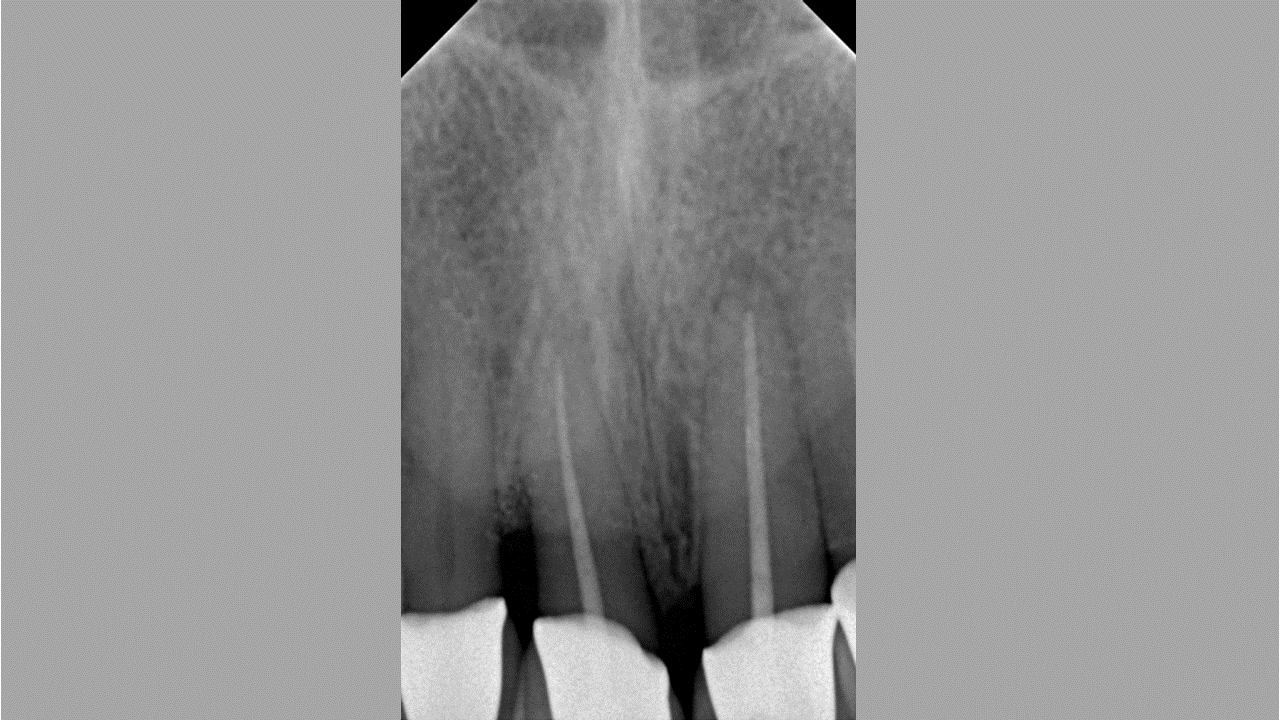

02/08 - Pre-operative radiograph of the defect reveals a deep intrabony defect on tooth 11.Non-contained intrabony defect treated with the simplified papilla preservation flap in conjunction with Straumann® Emdogain® and a particulate bone grafting material - Prof. Dr. Dr. A. Kasaj